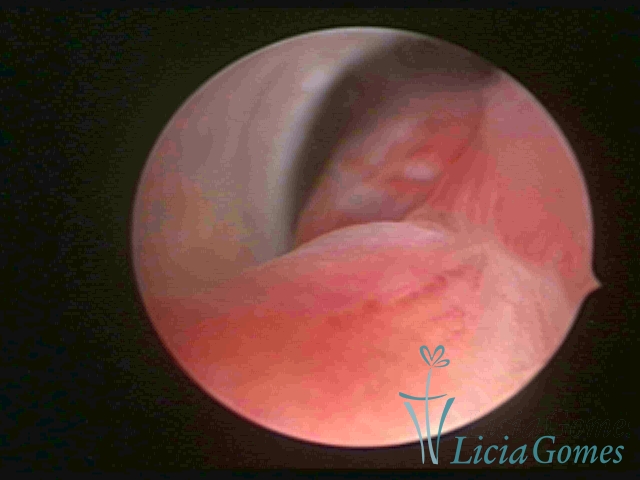

ENDOCERVICAL POLYPS

Benign tumors resulting from the reactive focal proliferation to inflammatory processes or hyperestrogenism situations, which may be sessile (with a large implantation) or stalked.